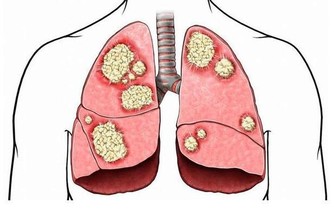

2、免疫力低下

嘴上長泡,暗藏6種致命疾病,做對5件事清火排毒!

有些人唇皰疹的發病率可能為一年兩次,而有的人可能每個月都會有唇皰疹的症狀。而反復發作的病人是終身攜帶病毒,病毒已經躲到神經結裡面了,當人處於比較疲勞的狀態,抵抗力下降,病毒又會活躍而發病,所以,這類患者則屬於復發性單純皰疹。

當你出現嘴邊長泡,或者口腔潰瘍、感冒、鼻炎等問題,並且都是經常反复,老不好時就要留心免疫力的問題了。